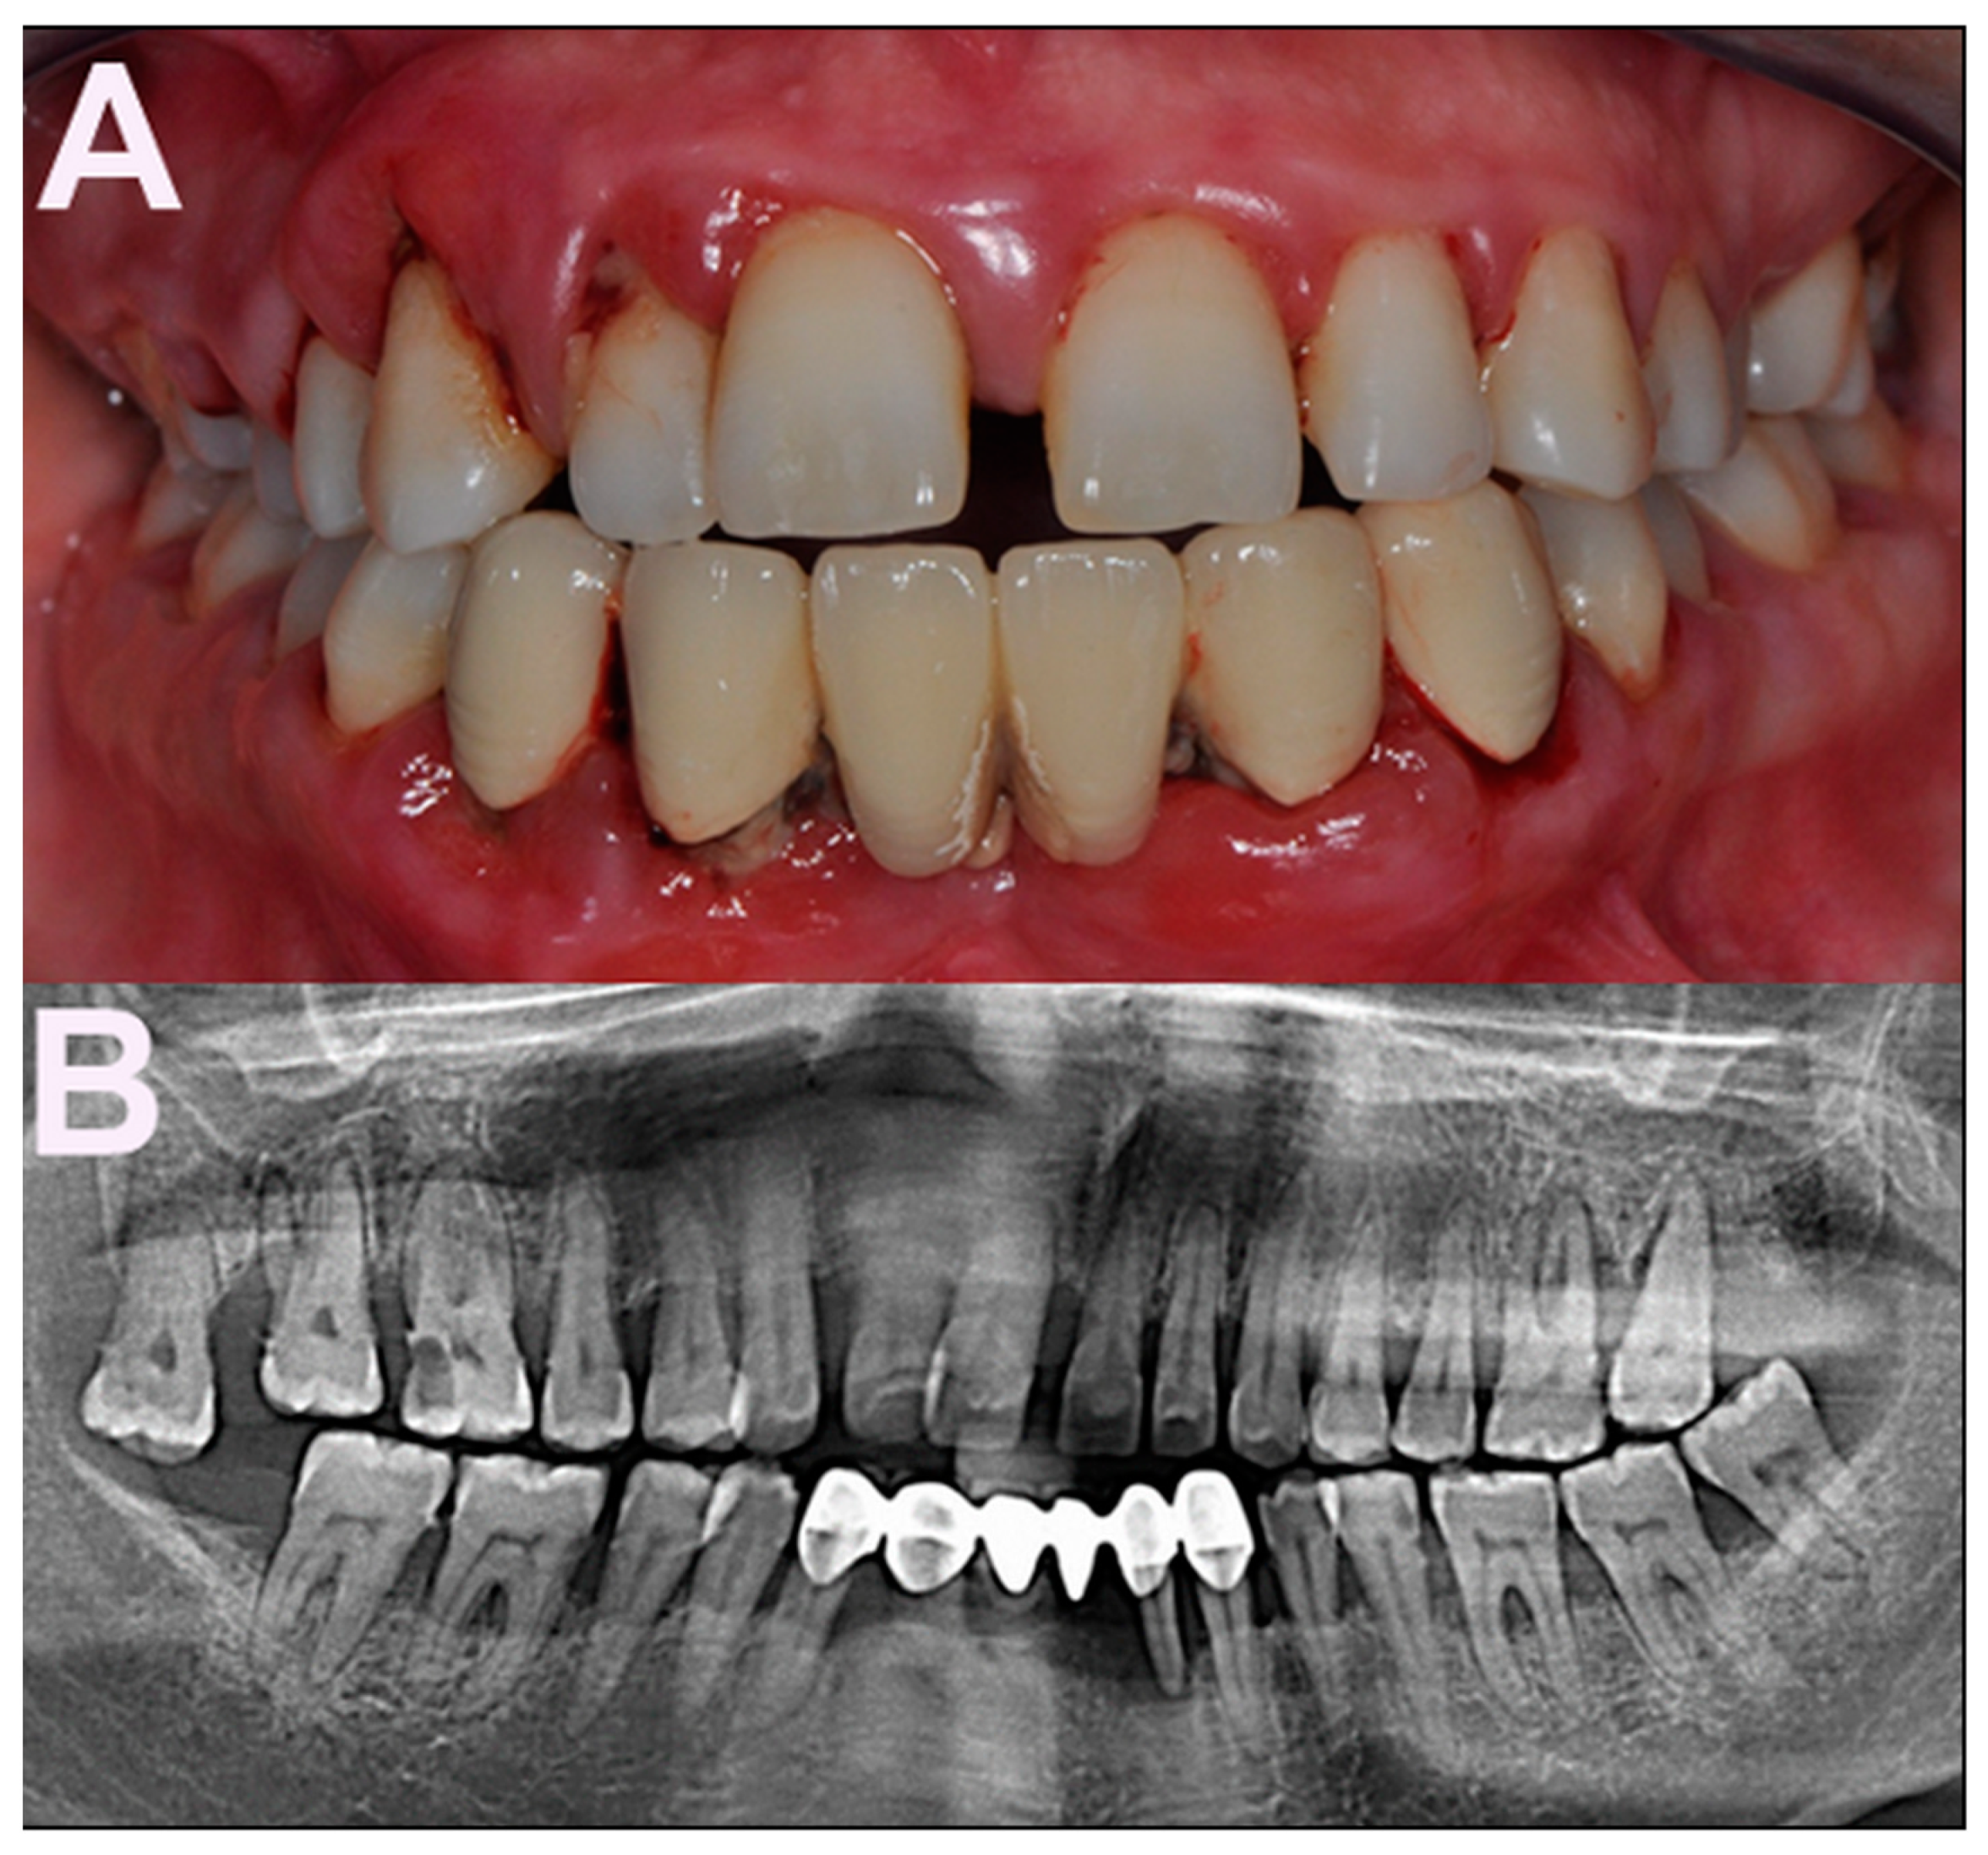

Periodontitis is a chronic inflammatory disease of the tooth-supporting tissues, and is characterized by progressive and irreversible breakdown of the periodontal ligament and the surrounding alveolar bone. The main features of the disease are attachment loss—which refers to the apical migration of the dentogingival junction—and bone resorption, leading to pocket formation (pathologically deepened gingival crevice) and increased tooth mobility (Figure 1A,B) [1].

Figure 1.

(A) Clinical appearance of advanced periodontitis in a 32-year-old, otherwise healthy, female patient. Heavy dental biofilm deposits and signs of gingival inflammation are clinically visible. (B) Panoramic radiograph of the patient reveals generalized alveolar bone destruction and its severity (by courtesy of Mustafa Yilmaz, Biruni University, Istanbul, Turkey).